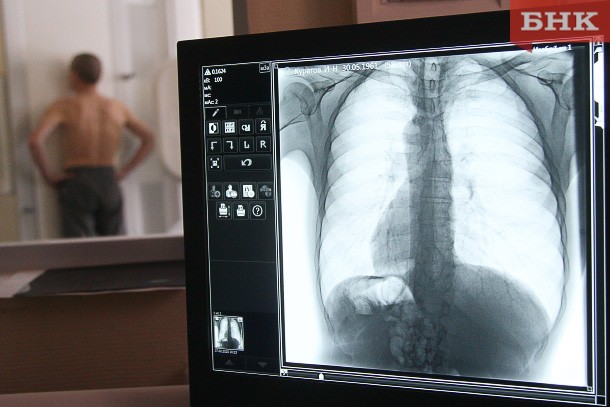

В Коми в десяти больницах появятся новые флюорографы, еще в пяти — маммографы

Центр обеспечения организации и проведения торгов разметил на сайте госзакупок аукцион на поставку цифровых флюорографов. Заказчиком выступает министерство здравоохранения Коми. Начальная цена контракта — 71 млн рублей, торги состоятся 30 марта. Срок поставки медицинского оборудования — в течение 90 дней с даты заключения договора.

В описании говорится, что назначение рентгеновской скрининговой системы — профилактические и диагностические исследования органов грудной клетки при заболеваниях легких, грудного отдела позвоночника, ребер, сердца. Вариант исполнения флюорографа — стационарный, без рентгенозащитной кабины. Его пропускная способность должна составлять не менее 60 человек в час.